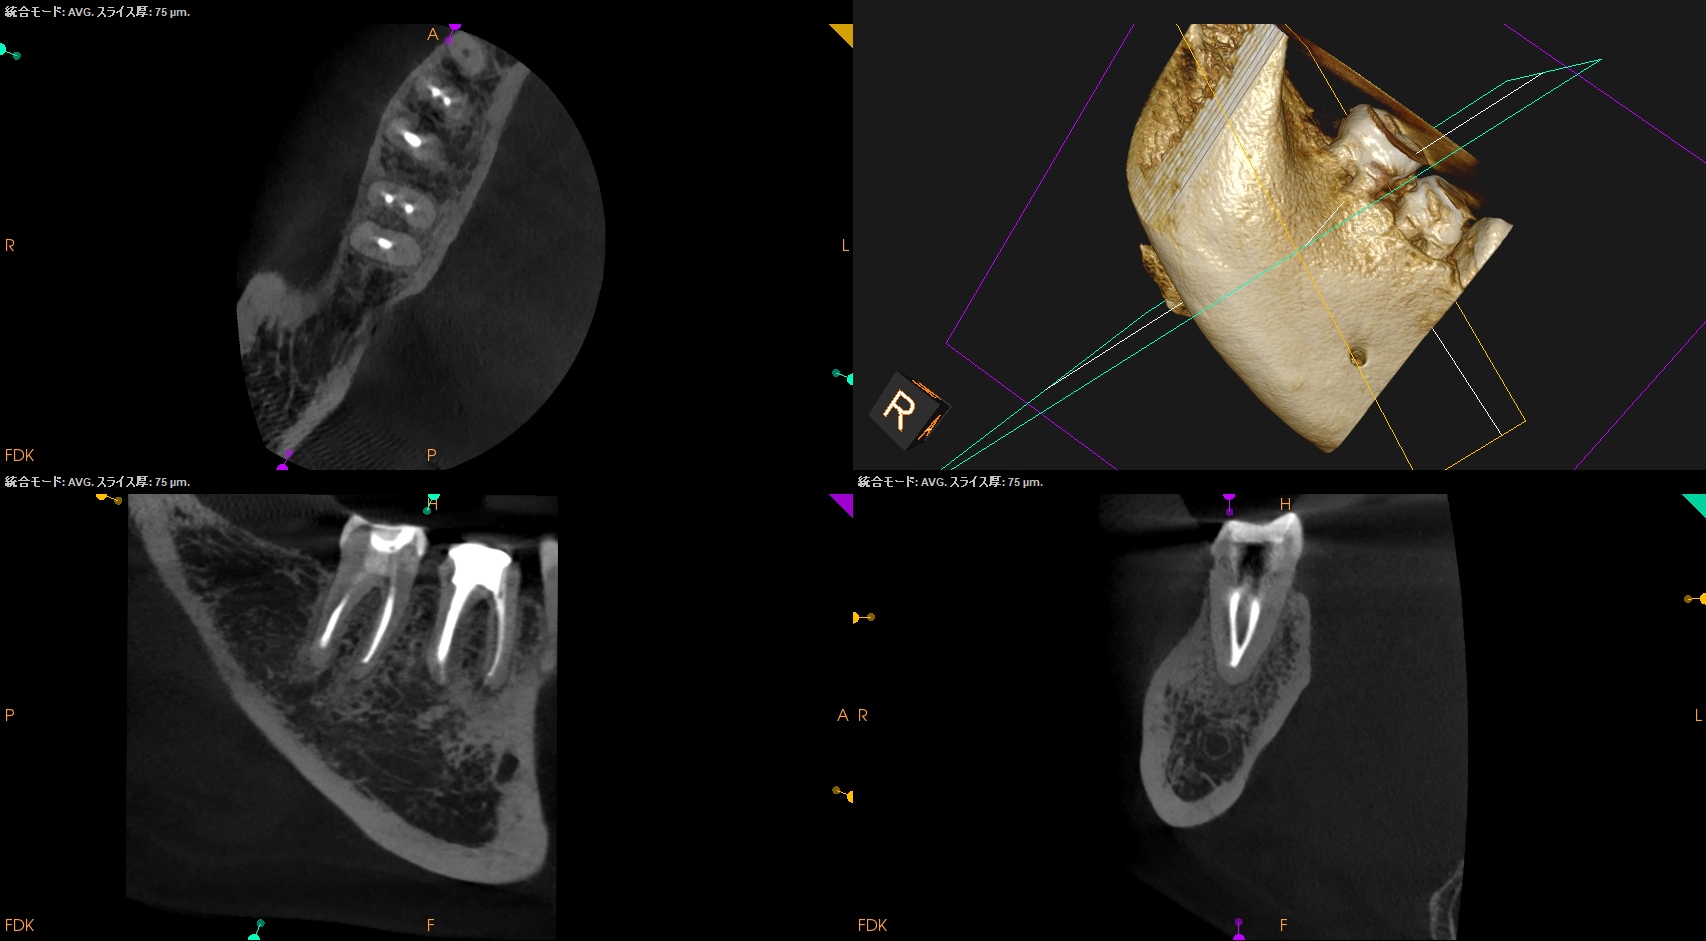

#31 RCT+Core build up(2025.9.12)

MLをメイン根管にし、MBがそこに合流する形式とした。

MLはMAFは当初は#40.04であったが#60.02に変更した。

炎症がまだ残存していると考え、MAFを#60.02まで上げた。

根充してPA, CBCTを撮影した。

MB

ML

D

問題はないだろう。